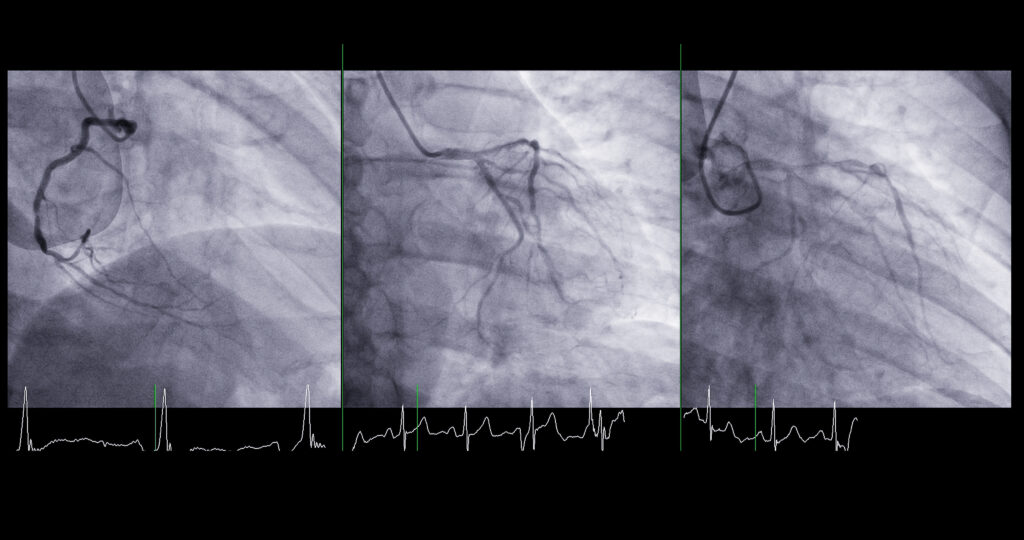

Right heart catheterization

If the results of initial diagnostic tests below point to PH, your doctor will schedule this more involved test. The right heart cath is the only test that directly measures the pressure inside the pulmonary arteries, and it should be done in all patients at least once to confirm a patient’s diagnosis of PH.